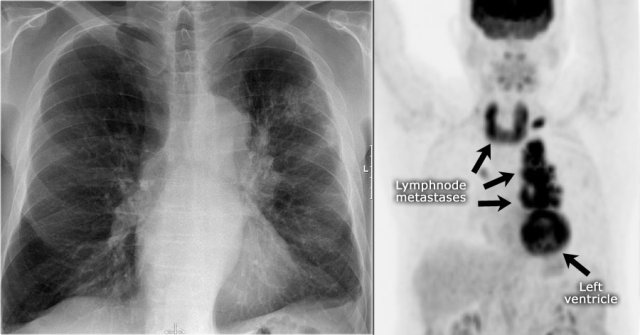

Here another case.

On the PA-film a mass is seen that fills the aortopulmonary window.

The PET better demonstrates the extent of the lymphnode metastases in this patient.

Final diagnosis: small cell lungcarcinoma.